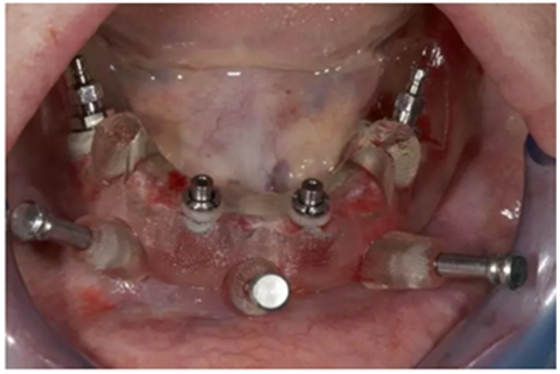

使用內(nèi)錐形連接引導(dǎo)式持釘器在下頜前牙區(qū)植入NobelReplace CC植體。

4枚NobelReplace CC植體均已植入完成:前牙區(qū)植入NP 3.5*13mm植體并裝配引導(dǎo)式基臺以固定導(dǎo)板,后牙區(qū)植入RP4.3*16mm植體并裝配內(nèi)錐形連接引導(dǎo)式持釘器。